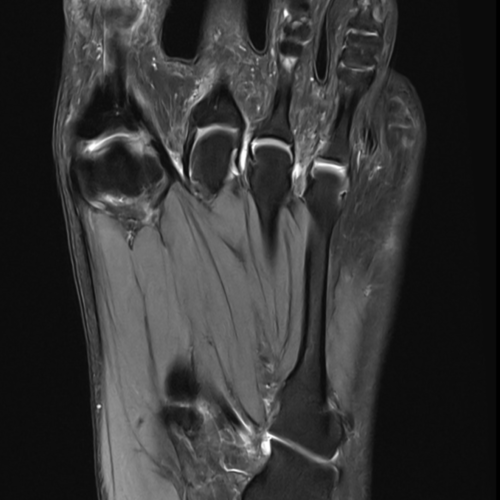

Quand pratique-t-on une IRM du pied ?

Cet examen est réalisé en cas de douleurs, traumatismes pour analyser :

- les os du pied :

Tarse : Talus (astragale), Calcaneum, Naviculaire, Cuboïde, Cunéiforme médial, Cunéiforme intermédiaire, Cunéiforme latéral

Les 5 métatarses

Les phalanges (orteils)

Quels sont les résultats possibles d’une IRM du pied ?

Cette examen permets de diagnostiquer:

- Fractures notamment de fractures de fatigues

- Entorses et lésions ligamentaires : notamment entorse de Chopart ou du Lisfranc

- Pathologies nerveuses : notamment névrome de Morton

- Pathologies tendineuses : notamment tendinite du tendon d’ Achille, aponévrosite plantaire

- Pathologies articulaires : arthrose, polyarthrite rhumatoïde

- Nécrose osseuse

- Kystes arthro-synoviaux